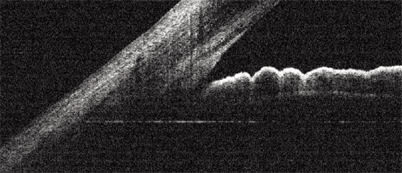

RTVue produces images at a 5-micron resolution, allowing unprecedented views of the angle.

Components of a cornea transplant are precisely presented in this RTVue OCT scan.